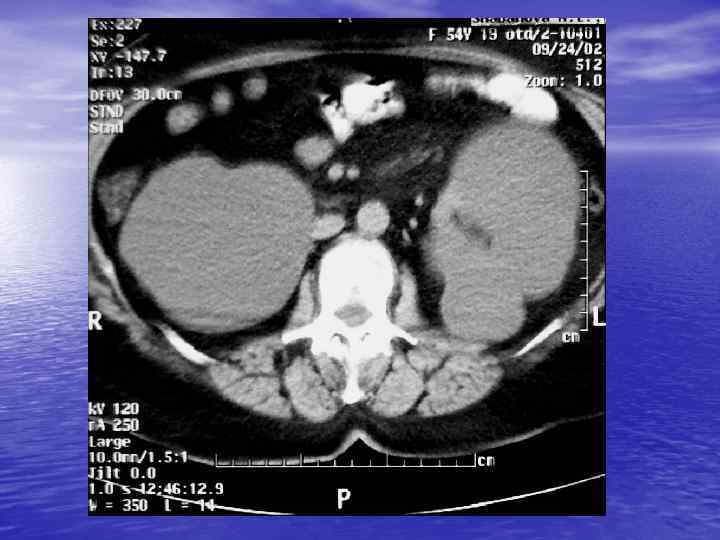

Анализ изображения: üструктурный (анатомический) - оценка морфологии üденситометрический - оценка плотности ткани

Структурный анализ Оценка основных макроскопических признаков: - положение - форма - размеры - характер контуров и структур патологически измененных участков

Денситометрический анализ Определение основных видов патологических образований: - обызвествленных - мягкотканных - жидкостных - жиросодержащих - воздухсодержащих

Денситометрия